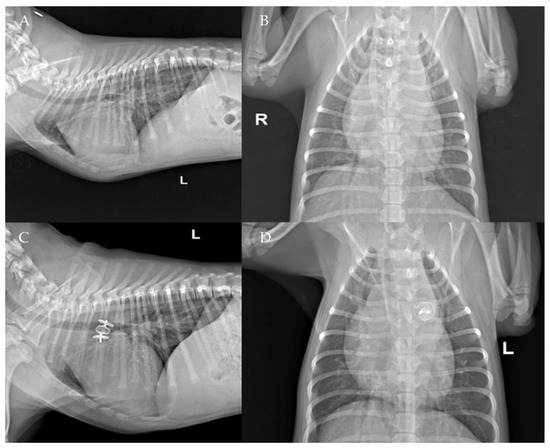

Figure 9. Pre-procedure (A,B) and post-procedure (C,D) left lateral and dorso-ventral thoracic radiographs of Case 2. L: left; R: right.

The thoracic radiographs performed before and just after the procedure showed a reduction in the cardiac silhouette as well as significant reduction of the over-circulation vascular pattern for all dogs (Figure 8, Figure 9, Figure 10, Figure 11 and Figure 12).